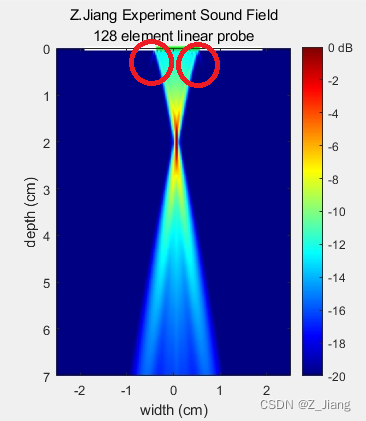

下面,我仿真一个128晶元的线阵,3.8厘米宽度的线阵探头,进行完整一帧图像扫查的声场情况;

顶部白线区域表示探头孔径,绿线位置表示发射时,实际激励晶元的位置。

注意对比一下相控阵探头偏转时的grating lobe,线阵就会小不少。